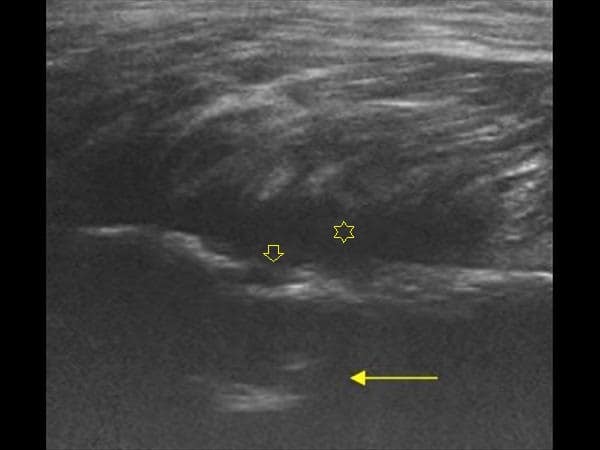

Apxe Brodie + Mất liên tục màng xương

Apxe Brodie + Mất liên tục màng xương - Phù nề mô mềm

Viêm xương tủy

» Thông tin: Nam giới – 34 tuổi.

» Lâm sàng: Sưng đau khớp gối.

# Apxe Brodie / Mất liên tục màng xương – Phù nề mô mềm.